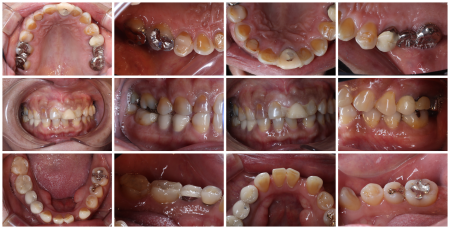

まずは右上前歯2本に精密な根管治療を行うために、治療する歯のみをゴムのシートで保護する「ラバーダム防湿」を施し、唾液や細菌が入らないよう清潔な環境を整えてから細部まで丁寧に処置しました。

その後、上の歯すべてに仮歯である「プロビショナルクラウン」を作製し、噛み合わせや歯ぎしりをした際の歯の当たり具合などをしっかり確認して形を整えたあと、プロビショナルクラウンの形に応じて最終的な被せ物を装着しています。

被せ物については、口を開けた時に特に目立つ前歯6本(右上犬歯/3番~左上犬歯)は患者様と相談した結果、耐久性と審美性に優れた自費の被せ物「ジルコニアクラウン」を選択されています。

欠損していた左上奥歯(第2大臼歯/6番)には両隣の歯を土台にして橋渡しのように被せ物を入れる保険の「ブリッジ」がもともと入っていましたが、今回前歯同様、ジルコニアクラウンでやり替えを行いました。

最後に、左右上の歯2本(第1小臼歯/4番)は保険の白い被せ物「CAD/CAM冠」を、右上奥歯2本(第1大臼歯、第2大臼歯)も保険の金属製の被せ物をそれぞれ装着し、治療を終了しています。